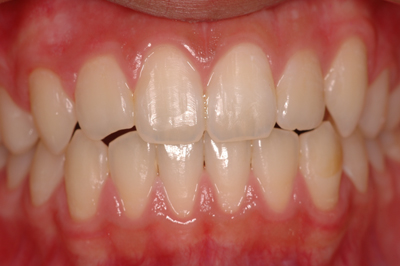

矯正治療例

施術前

施術中

施術後